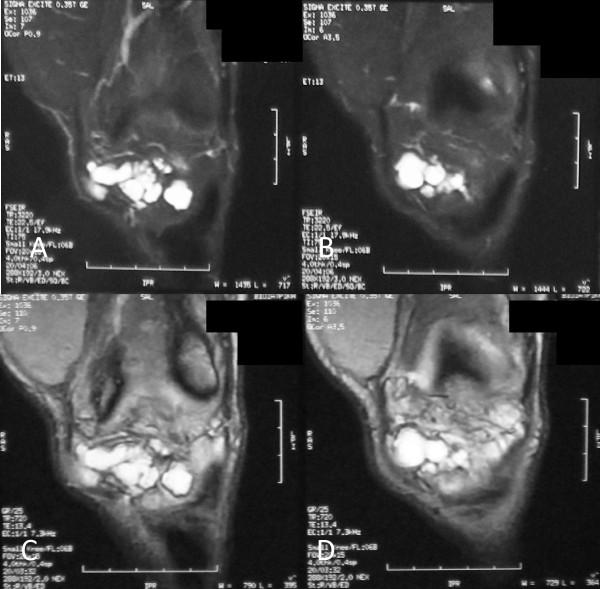

We report the case of a large infrapatellar fat pad ganglion in a 37-year-old Greek man with chronic knee discomfort. The ganglionic cyst originated from the infrapatellar fat pad and had no intrasynovial extension. The final diagnosis was determined with magnetic resonance imaging of the knee, and the lesion was treated with surgery.

我们报告一例37岁希腊男性患有髌下脂肪垫大型神经节囊肿且伴有慢性膝关节不适的病例。神经节囊肿起源于髌下脂肪垫,无滑膜内延伸。通过膝关节磁共振成像确定最终诊断,并对病变进行手术治疗。